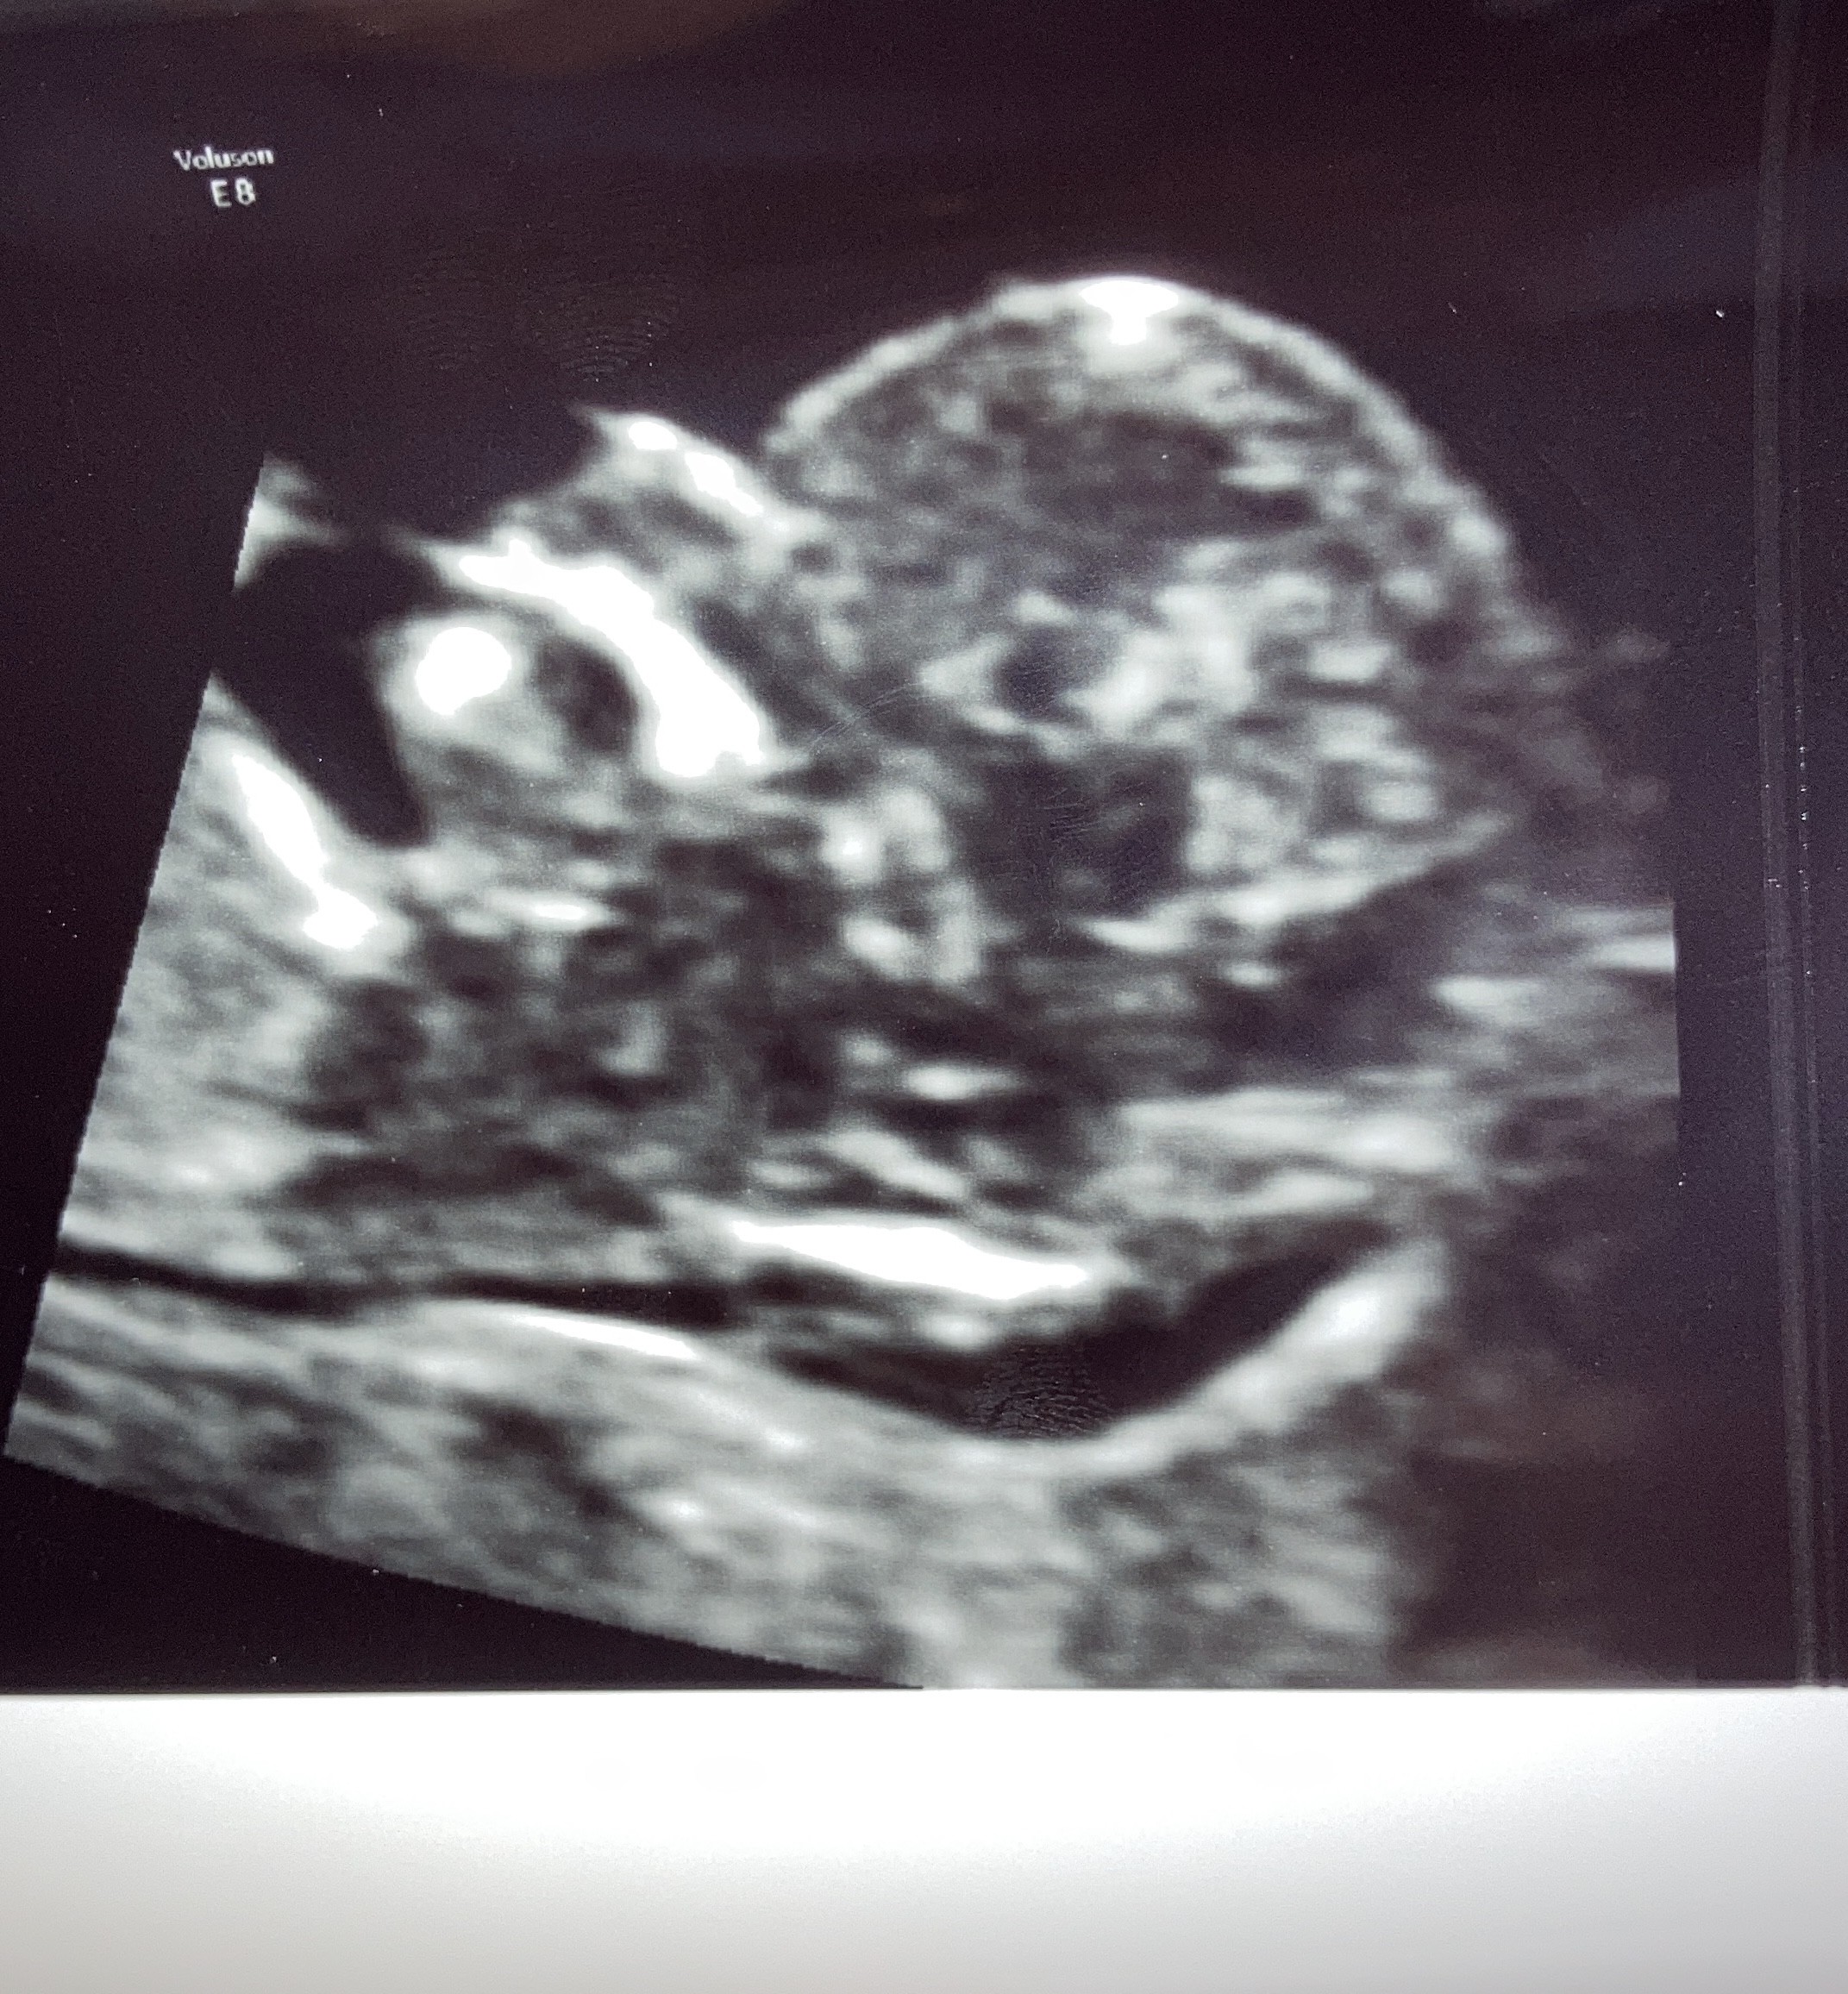

Dziewczyny dzidzia ma się dobrze ☺ Prawdopodobnie córcia ☺🤗 czekam na wynik pappa z krwi ale z usg jest oki ☺

ED005C64-F14D-49D8-99BE-BFB2C35D579E.jpeg